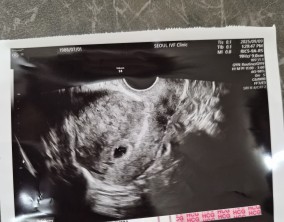

나에게 찾아온 작은 동그라미

병원만 오면 긴장감이 맴도는편인데 들어가자마자 밝게 맞아주는 데스크 선생님들, 편안하게 대해주는 간호사분들 덕분에 분위기가 금세 풀어졌어요. 그리고 이경훈 원장님은 꼼…